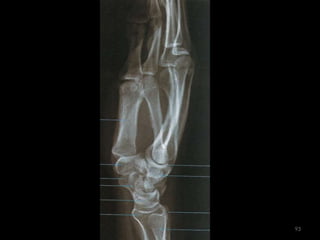

antebraço80

Incidência AP/PA do antebraço81

82

83

Incidência lateral do antebraço: látero-medial84